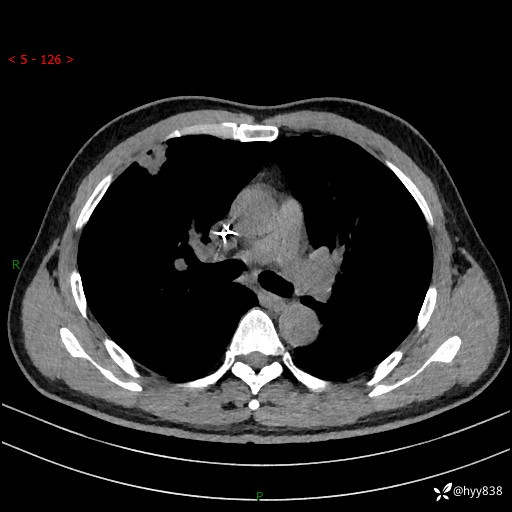

现病史:者10余天前因胸闷就诊于我院心血管内科,行胸部CT提示右肺上叶结节(24mm×16mm),考虑肿瘤性病变可能。无畏寒、发热、盗汗,无咳嗽咳痰,无咯血,无胸痛,无呼吸困难等不适,未予特殊处理。今为求进一步诊治,前来我院就诊,门诊以“肺结节待查”收住入院。 患者自起病来精神、食欲、睡眠尚可,体力下降,体重无明显变化。

胸部CT平扫+增强